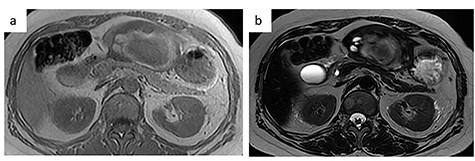

A 56-year-old woman presented to another hospital with acute abdomen. Computed tomography (CT) examination demonstrated a tumor 10 cm in diameter that protruded from the left lateral segment of the liver, with evidence suggestive of rupture of the liver tumor (Fig. 1). Since the patient was in good general condition, she was referred to our hospital for further evaluation. Her blood biochemical parameters when she was referred to our hospital were hemoglobin: 11.6 g/dl, albumin: 3.4 g/dl, γ-globulin: 18.5% and anti-acetylcholine receptor antibody: <0.3 nmol/L. Dynamic CT presented a liver tumor 10 cm in diameter, which was located at the left lateral segment of the liver, with a clear margin. A mass with an irregular margin was also identified in the anterior mediastinum (Fig. 2). On percutaneous angiography, since obvious extravasation of the contrast medium could not be identified, the arteries of the left lateral segment were embolized to prevent re-bleeding. Although a definitive preoperative diagnosis could not be made using magnetic resonance imaging (MRI) (Fig. 3), fluorodeoxyglucose positron emission tomography (FDG) showed increased FDG uptake in both the hepatic and anterior mediastinal tumors (Fig. 4). Although the liver tumor was suspected to be metastasis secondary to a thymoma based on the clinical findings, percutaneous tumor biopsy was performed to confirm the pathological diagnosis. The biopsy suggested malignant T-cell lymphoma or metastatic thymoma. In order to prevent re-rupture of the hepatic tumor, to confirm the pathological diagnosis and to potentially achieve a curative resection, the patient underwent laparoscopic left lateral segmentectomy (Fig. 5). Although the tumor was found to be adherent to the stomach, blunt dissection was possible. In addition, no peritoneal dissemination was detected. The surgical duration was 212 min and estimated blood loss was 50 ml. The liver tumor was pathologically diagnosed as metastatic thymoma type AB (Fig. 6). The patient’s postoperative course was uneventful and she subsequently underwent radical thymectomy 3 months after the liver resection. The thymic tumor was pathologically diagnosed as thymoma type B2. Currently, 30 months after thymectomy, she remains free from tumor recurrence.

Contrast-enhanced CT. (a) Abdominal CT: a solitary liver tumor, 10 cm in diameter, was located in the left lateral segment of the liver. The tumor had a clear margin, with tumor enhancement in both the arterial and portal phases. (b) Chest CT: an enhanced tumor with an irregular margin was detected in the anterior mediastinum. The tumor had a maximum diameter of 4.5 cm.